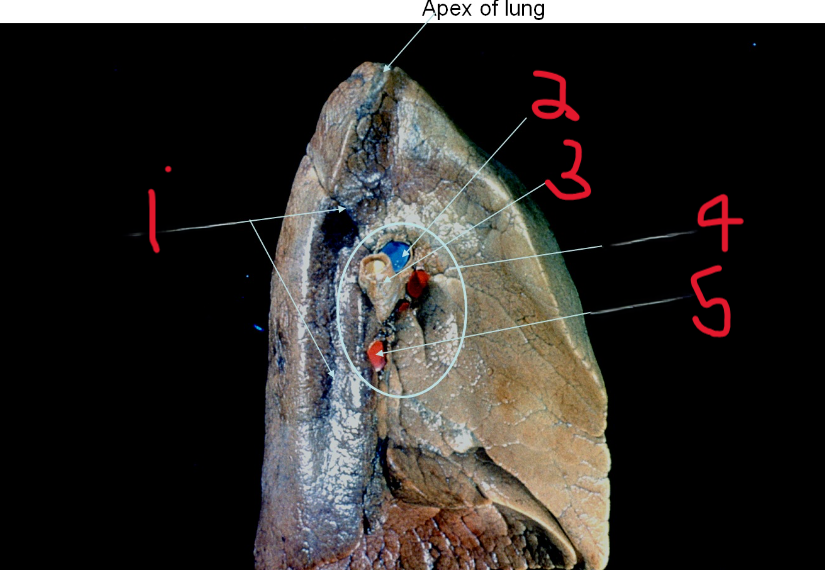

Aortic impression

What is depicted by #1

Pulmonary artery

What is depicted by #2

Left main bronchus

What is depicted by #3

Hilum of lung

What is depicted by #4

Pulmonary vein

What is depicted by #5